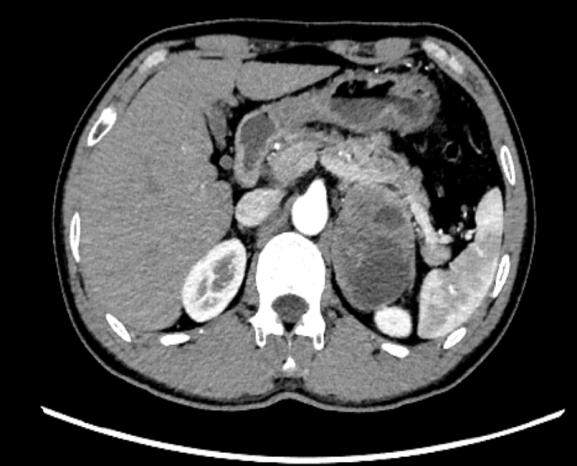

近日,我院接诊一位47岁患者王某,因持续头痛、头晕4天前来就诊。经CT检查发现,左侧肾上腺区存在一类圆形混杂密度肿块,大小约5.2cm×7.8cm×6.1cm,边界清晰,密度不均,增强扫描显示不均匀强化,内部可见片状无强化坏死区,初步诊断为嗜铬细胞瘤。